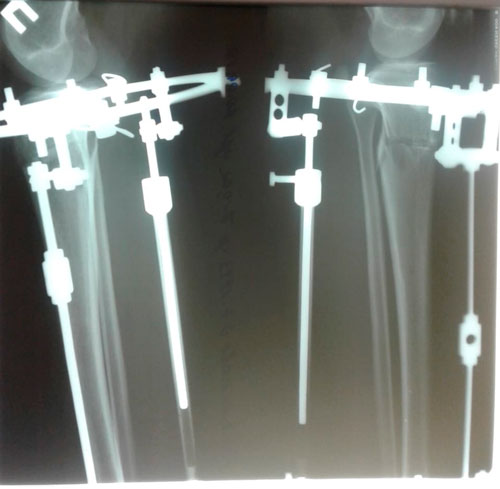

в процессе работы

Дата операции - 27.03.2019г.

Дата снятия аппаратов - 20.06.2019г.

Срок сращения - 83 дня.